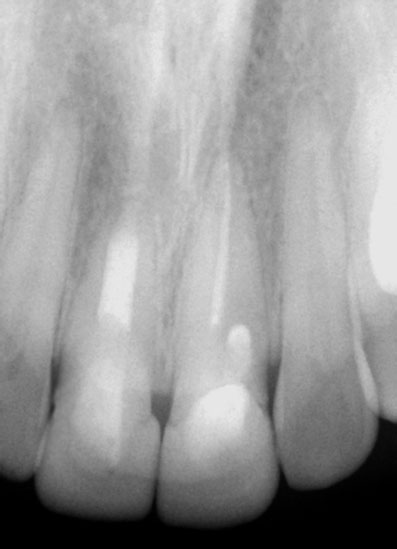

Pre-op

Pain in mandibular first molar after endo. Previous dentist unable to locate mesial canals. Obturated only the distal canal. Patient has generalized periodontal problems as well.

Pre-op, EDTA for 1 minute, After 1 minute EDTA

Red arrows show the two “white spots” indicating the calcified mesial canals.

Missed second distal canal (red arrow)

Pre-op & Post-op